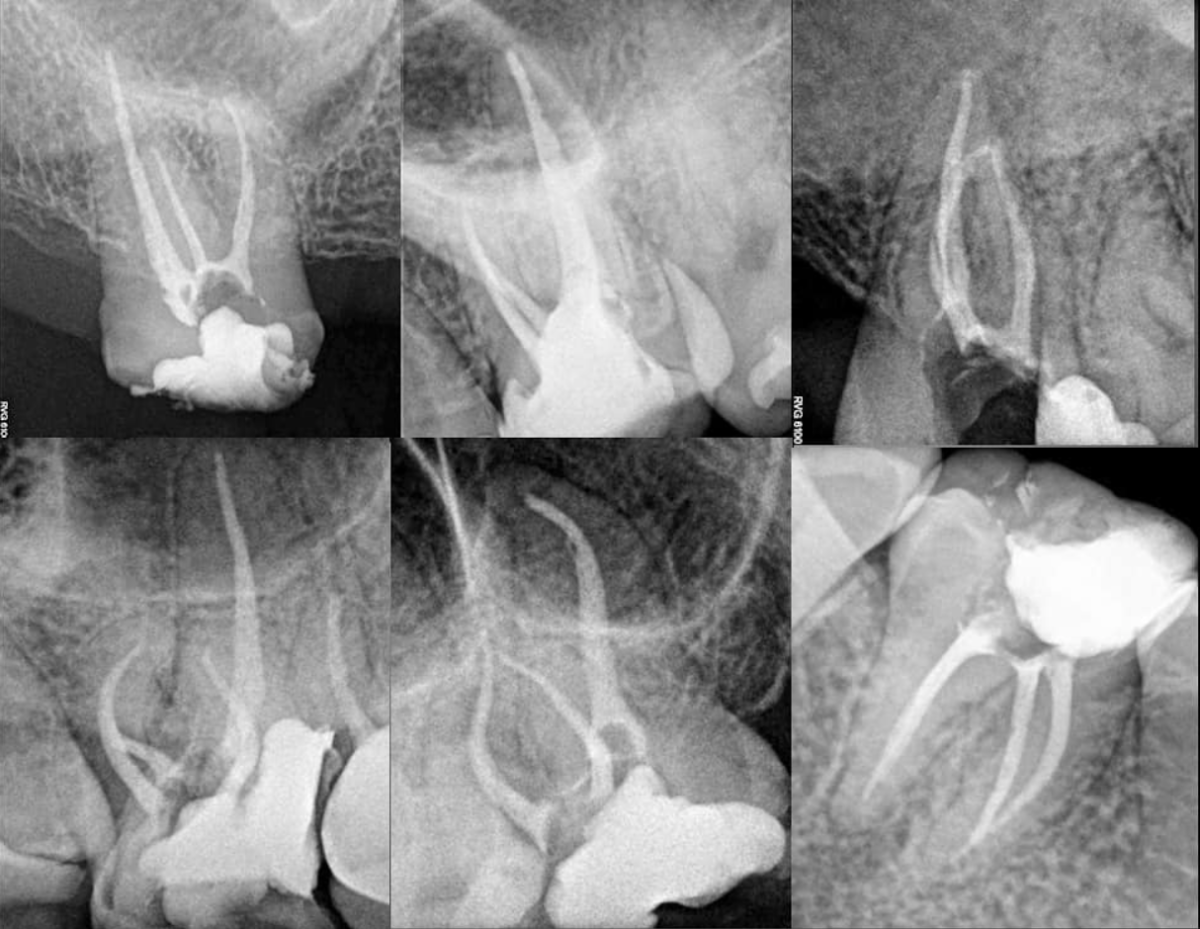

Her dişin kök sayısı ve kök anatomisi farklıdır. Ön dişler genelde tek köklü, üst küçük azılar iki, azılar ise üç veya dört köklüdür. Bu kökler içinde ise değişik sayıda kanal vardır. Örneğin tek köklü bir alt kesicinin içinde her zaman tek kanal olmayabilir. Azı dişlerde ekstra kanallar çıkabilir. Bu nedenle her dişin kanal tedavisi ayrıdır.

Kök ve kanal sayısı, köklerin anatomisi ve dişe daha önce kanal tedavisi yapılıp yapılmaması belirler. Yapılmış bir kanal tedavisini düzeltmek, hiç kanal tedavisi görmemiş bir dişe kanal tedavisi yapmaktan daha zordur. Bu yüzden dişe ilk kez yapılacak kanal tedavisinin düzgün yapılması çok önemlidir.

İltihabın sebebi kök kanal sistemindeki mikroorganizmalardır. Uygun bir kanal tedavisi ile ortam mikroorganizmalardan arındırılırsa iltihabın iyileşme şansı oldukça yüksektir. Bu konuyla ilgili örnek vakaları inceleyebilirsiniz.

Eğer daha önceki tedavi başarısız olmuşsa sebep araştırılmalıdır. Malesef gördüğümüz başarısız kanal tedavilerinin çoğu yetersiz şekillendirme, temizlik ve doldurmadan kaynaklanmaktadır. Bu durumda eğer dişte kalıcı hasar meydana gelmemişse kanal tedavisi yenilenebilir. Bu işleme “retreatment” yada “kanal tedavisi tekrarı” denir.